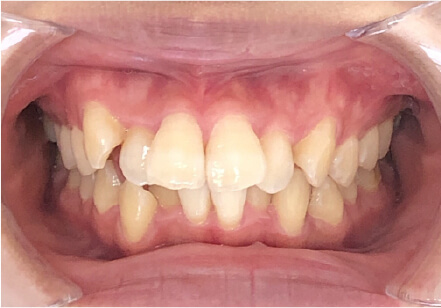

叢生の症例

9歳

/

女性

相談内容

マイオスマイルからの移行

カウンセリング・診断結果

上11捻転、上33スペース不足、インビザで歯列矯正

治療内容・方法

全額アライナー矯正 クリアコレクト

術後の経過・現在の様子

リンガルアーチ使用

治療のリスク

痛み・歯根吸収・歯肉退縮・虫歯・後戻り

費用・治療期間

(マウスピース矯正のみ)440,000円+220,000円 月々27,500円、9ヶ月+myo1年10ヶ

トレーニングなど